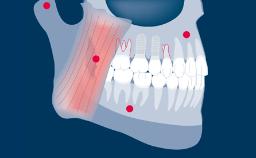

O clínico que pratica implantodontia é confrontado com diferentes situações clínicas, que variam de um único dente ausente, a um espaço edêntulo com vários dentes ausentes até completar rebordos totalmente edêntulos. Uma vez estabelecido um plano de tratamento completo, diferentes desenhos de configurações podem ser possíveis para próteses implantossuportadas. Cada desenho da prótese tem suas vantagens e desvantagens. O desenho da prótese deve basear-se na condição clínica para garantir que o número apropriado de implantes seja instalado nas posições protéticas corretas usando implantes com dimensões apropriadas.

- espaços dentais unitários

- espaços edêntulos curtos

- espaços edêntulos extensos

- rebordos edêntulos